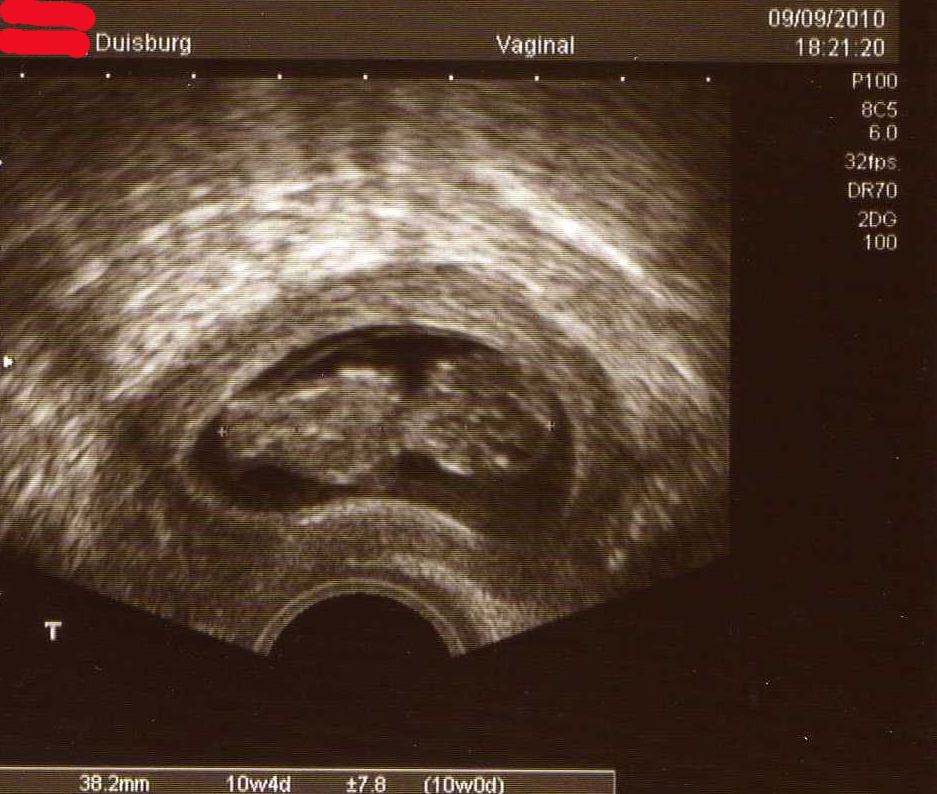

nur kurz: alles bestens, alles zeitgemäß, wir haben den Herzschlag auch heute hören können, Arme Beine alles dran.

Baby002.jpg

@Muggelchen, was für eine Figur eurer Krümmel macht! :D